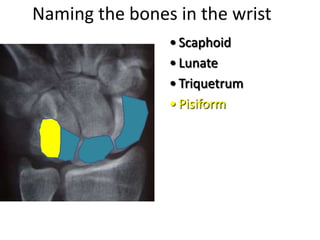

- Naming the bones, joints, tendons, nerves and skin landmarks of the hand and wrist.